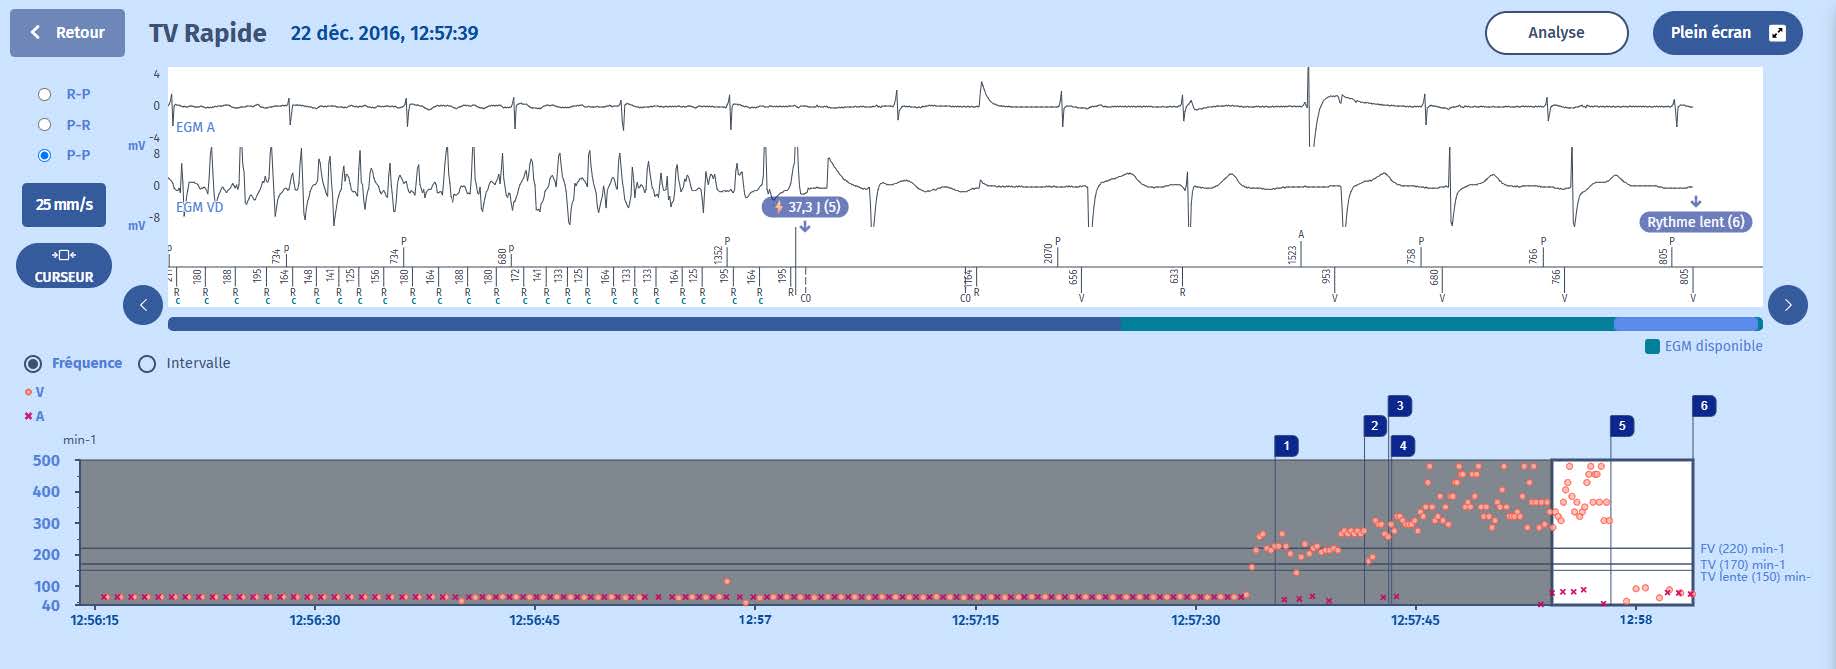

5 La deuxième ligne de thérapie consiste en des chocs, d'où la charge des condensateurs.

6 La FV s'est poursuivie tout au long de la charge, le dispositif a pu confirmer la charge d'un cycle à l'autre et à la fin de la charge, un cycle de 195 ms confirme que la FV se poursuit, et un choc est donc délivré (37,3 J).

7 Le premier signal après le choc est l'ouverture des chaînes de détection (pour l'implant, l'intervalle de couplage de ce cycle est de 164 ms : l'intervalle post-choc est de 1164 ms qui est égal à la période de suppression d'une seconde plus 164 ms), les 6 cycles

suivants sont lents et mettent fin à l'épisode.